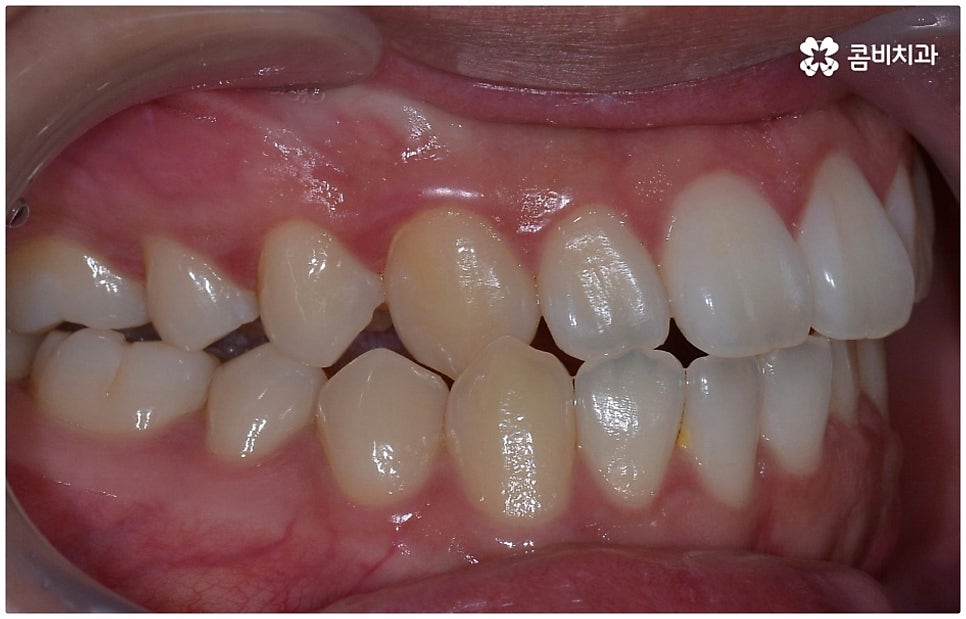

위아래 치아의 교합이 잘 맞지 않는 부정교합을 가지고 있으면 외적인 자신감이 떨어질 뿐 아니라 기능적으로 잘 씹지 못하고 말을 할 때도 발음이 부정확해지는 문제가 생길 수 있기 때문에 교정 치료 등으로 바로잡아 줄 필요가 있어요. 부정교합은 1급, 2급, 3급으로 나눌 수 있는데 오늘은 특히 부정교합 3급 중 절단교합 케이스에 대해 자세하게 알아보려고 하고 있습니다.

부정교합 3급 이란 입을 다물었을 때 아래 어금니가 윗 어금니보다 전방에 위치한 경우를 가리키는 것으로 그 중 절단교합은 이 상태에서 위아래 앞니 끝과 끝이 맞닿는 교합을 의미하는 거예요. 이에 비해 정상적인 교합은 어금니는 똑바로 맞물리고 윗 앞니는 아랫 앞니를 살짝 덮는 정도로 겹쳐지면서 자연스럽게 조금 앞으로 나와 있는 상태를 말하고 있습니다.

이때 심하지 않은 절단교합의 경우 환자분들의 입장에서는 하악이 상악보다 상대적으로 튀어나와 주걱턱처럼 보이는 정도가 그렇게까지 크지는 않다 느끼실 수 있는데요. 특히 또 다른 부정교합 3급 케이스 중 하나인 반대교합 (아래 앞니가 윗 앞니보다 더 앞으로 나가 거꾸로 물리는 경우) 과 비교해 보면 더욱 심각하게 생각되지 않을 수 있어요.

물론 교정 치료에 적기가 정해져 있는 것은 아니기 때문에 성인 이후 중장년 환자분들이라도 교정 치료가 불가능하지는 않으며 상황에 따라 비수술적인 방법으로도 얼마든지 불편함을 줄일 수 있는 경우가 있으니 정확하게 진단한 후 각자에게 맞는 교정 계획을 세워 무리하지 않게 치료를 진행하시길 바라고 있어요. 특히 턱관절과 관련된 부분을 개선하기 위해서는 양악 수술 밖에 방법이 없는 것이 아닌가 생각하셨던 분들이라면 먼저 치과에 내원하셔서 검진과 상담부터 진행해 보시면 마음의 부담을 덜 수 있어 좋을 거예요. 부정교합 3급 치열 (절단교합과 일부 반대교합이 병행되어 있음) 을 가지고 있는 성인분도 교정 치료를 통해 훨씬 자연스럽게 개선이 가능할 수 있으며, 관련 기술 개발 및 미니스크류 등 여러 장치의 발전을 통해 예전에는 적용이 어려웠던 케이스들도 이제는 교정 치료의 도움을 받을 수 있습니다.